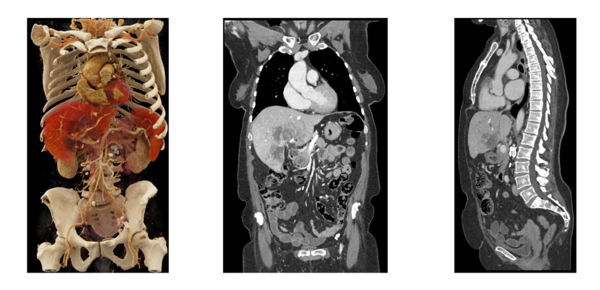

フォトンカウンティング検出器を搭載した最新の Dual Source CT(2つのX線管と検出器を搭載したCT)といった大きな特徴を活かしたスペクトラルイメージングにより,1秒未満といった短い時間での70cmを超える広範囲の撮影,心臓など動きのある臓器においても高精細な画像の取得が可能となる。

さらに被ばく線量を約100分の1*1,2に減少した撮影を実現し,患者や検査を受ける方の負担を減らしつつ正確で包括的な検査が可能となる。その応用範囲は,腫瘍や心臓の診断から肺のフォローアップ検査まで,幅広く多岐にわたる。

「NAEOTOM Alpha」で撮影した全身の腫瘍検査 エラスムスメディカルセンター 提供